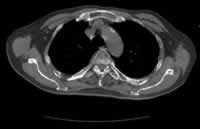

患者1年前从楼梯上不慎摔倒,半月后病人搬动花盆后出现腰背部疼痛。就诊于当地医院,胸腰椎X线片示:T12压缩性骨折。服中药治疗,服药6天后出现食欲下降,第14天起出现恶心呕吐,为胃内容物,无呕血。再次就诊,腹部 CT示胆囊炎、胆石症。胃镜示浅表性胃炎伴胆汁反流。肝功能、肿瘤指标、血尿淀粉酶均未见异常,血钙2.41 mmol/L。予以“奥美拉唑、头孢氧哌唑(先锋必)、甲氧氯普胺(胃复安)”等治疗后病情无明显改善,遂入院进一步诊治。查血常规示贫血(RBC 2.19×1012/L, Hb 74 g/L)。腰椎MRI示T12、 L2、 L3椎体压缩性骨折,以L3为甚,伴椎管狭窄,L4-5椎间盘突出。免疫球蛋白IgA 1060 mg/dl升高(↑)IgM 44.50 mg/dl降低(↓)。血沉(ESR)114 mm/h↑。 经氨基酸、脂肪乳营养支持,叶酸等纠正贫血后10天患者病情好转出院。出院诊断为“胸腰椎骨折,高免疫球蛋白血症(IgA)。”出院后病人病情稳定,无恶心呕吐,无腰背疼痛,能进行轻度体力活动。直至本次入院前2个月,病人再次出现腰部疼痛,呈进行性加重,行物理治疗疗效不佳,后又出现恶心呕吐不能进食。于两周前入住当地医院查血钙3.76 mmol/L,给予降钙治疗、营养支持、对症治疗后仍有呕吐腰痛,故收住我科进一步诊治。

入院查体 T 37.5 ℃,BP 150/80 mmHg,贫血貌,皮肤无黄染、皮疹和出血点。颈下、腋下及腹股沟可触及肿大淋巴结 ......